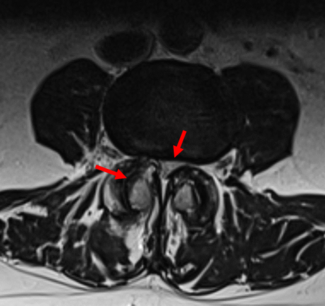

Le vertebre presentano posteriormente un anello (fatto di “peduncoli” e “lamine”) che formano, impilati fra loro come sono, un vero e proprio canale. Da oltre 90 anni è noto che il disco intervertebrale, una specie di cuscinetto ammortizzatore fra una vertebra e l’altra, a livello lombare (più che in altre sedi) può “sfiancarsi” posteriormente e andare a comprimere le più varie terminazioni nervose dolorifiche all’interno dell’angusto canale vertebrale.

Il canale ha una sezione di pochi centimetri quadrati e ospita nervi, legamenti, arterie, vene, grasso il sacco durale (o dura meninge) che avvolge le lunghe radici nervose che - uscendo dal canale vertebrale - si dirigono alla zona lombare, glutea e agli arti inferiori. Nel sacco è poi raccolto il liquido cerebrospinale (o liquido cefalorachidiano, o “liquor”): nel canale c’è una gran folla, come si vede.

Il "canale ristretto"

La compressione può avvenire anche da parte di deformità artrosiche che si formano nelle articolazioni (le “faccette”) che connettono posteriormente le vertebre fra di loro (immaginiamo le conseguenze di deformazioni delle nocche in una mano artrosica ma all’interno del canale vertebrale, rigido e poco spazioso).

Si parla allora di “canale ristretto” o “stenosi lombare”: una sindrome nella quale al dolore si associa una ridotta distanza di marcia. Dopo 50-300 metri “le gambe non vanno più”.

Ci siamo dimenticati che il canale vertebrale è foderato da un fitto reticolo venoso scoperto soltanto nel 1940. Anche lui può venire facilmente compresso e quindi dilatarsi, oppure si può dilatare se il flusso venoso non viene “smaltito” facilmente (come nel riposo, quando manca “pompa” muscolare, o in caso di insufficienza cardiaca o respiratoria). E se le vene diventano varicose creano anch’esse compressione. Inoltre il sangue al loro interno tende a ristagnare e una dolorosa flebite è in agguato. In breve, al dolore può contribuire la insufficienza venosa locale.